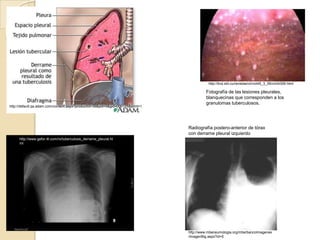

Fotografía de las lesiones pleurales,

blanquecinas que corresponden a los

granulomas tuberculosos.

Radiografía postero-anterior de tórax

con derrame pleural izquierdo